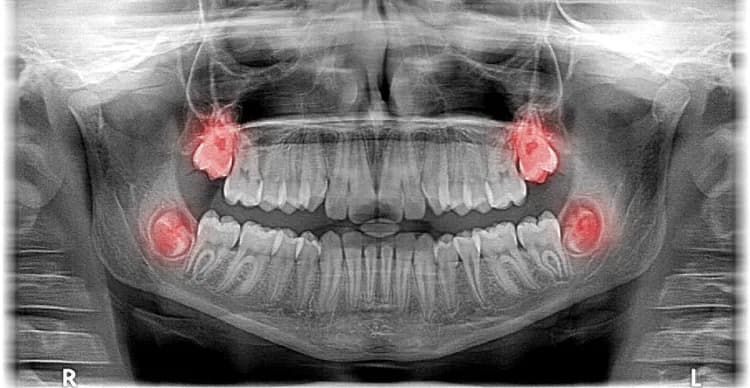

Ósemki, znane również jako zęby mądrości, mogą wyrastać w górnej szczęce. To ważne zrozumieć, że te zęby pojawiają się po każdej stronie łuku zębowego, co oznacza, że mogą rozwijać się zarówno w górnej, jak i dolnej części jamy ustnej. Zazwyczaj występują cztery zęby mądrości, po jednym w każdej ćwiartce łuku zębowego. Wyrastają one w miejscu za drugimi zębami trzonowymi, zwanymi siódemkami.

Zęby mądrości w górnej szczęce wyrastają z tyłu jamy ustnej, tuż za drugimi zębami trzonowymi. Te zęby zazwyczaj pojawiają się w wieku od 17 do 25 lat. Ich położenie jest kluczowe, ponieważ mogą wpływać na sąsiadujące zęby oraz na całą strukturę zgryzu. W górnej szczęce ósemki często mają więcej przestrzeni do wzrostu, co może prowadzić do ich prawidłowego rozwoju.

Zęby mądrości w dolnej żuchwie – różnice w wzroście

W dolnej żuchwie zęby mądrości również wyrastają za drugimi zębami trzonowymi, jednak ich wzrost może przebiegać inaczej niż w górnej szczęce. W dolnej żuchwie często występuje mniej miejsca, co może prowadzić do problemów z ich prawidłowym umiejscowieniem. Często ósemki w dolnej żuchwie są bardziej narażone na zatrzymanie, co oznacza, że mogą nie wyrastać całkowicie.

Wyrastanie ósemek, czyli zębów mądrości, może wiązać się z różnymi komplikacjami zdrowotnymi. Wiele osób doświadcza bólu, dyskomfortu oraz innych problemów, które mogą wynikać z niewłaściwego wzrostu tych zębów. Często ósemki mogą być zatrzymane, co oznacza, że nie mają wystarczająco dużo miejsca, aby w pełni się wykształcić. Takie sytuacje mogą prowadzić do stanów zapalnych, infekcji oraz uszkodzenia sąsiadujących zębów.

Inne potencjalne komplikacje obejmują torbiele, które mogą powstawać wokół zatrzymanych zębów, a także ich przemieszczenie, co może wpływać na zgryz. Warto zwrócić uwagę na te problemy, aby uniknąć poważniejszych konsekwencji zdrowotnych i zapewnić prawidłowy rozwój zębów. Regularne kontrole u dentysty są kluczowe dla monitorowania stanu ósemek i wczesnego wykrywania ewentualnych problemów.